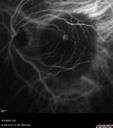

92 year old man The vision in the left eye has been declining for about 8 weeks. Prior to that the two eyes were similar. The left eye did have a prior retinal detachment. The RD was in the 1990's. It was repaired by Dr. Tom Ward. Dr. Cohen saw the patient afterward and did a lot of treatment for retinal tears. Medical Hx: BPH. Congestive Heart Failure. Hypertension, Systemic. Pure Hypercholesterolemia, Unspecified. Surgical Hx: Tonsillectomy. Appendectomy. Herniorrhaphy. Cataract Surgery. Systemic Meds: Avodart 0.5 mg. Calcium 500mg. Digitek 125mcg. Eliquis 5mg. Entresto 24mg. Lasix midodrine 5mg. Ocuvite. Propafenone 150mg. Vitamin D. Zocor 20mg. VA 20/25 OD, 20/200 OS IOP 8 OD, 12 OS

Wet AMD - Type 1 CNVM - RAP lesion69 views92 year old man with vision loss and very high PED. Because of worry about a PED tear, patient was treated with avastin, then lucentis, then eyelea, then vabysmo (progressively stronger meds)00000